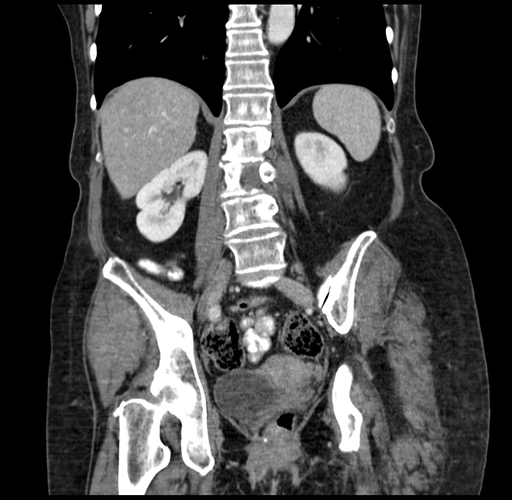

Pre-Chemo: Coronal Venous

Coronal Venous